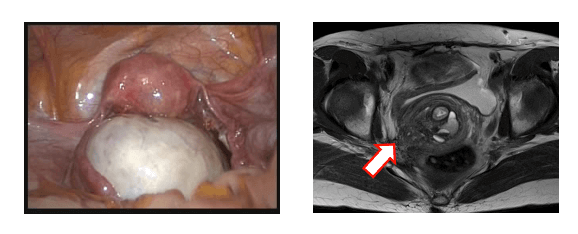

Endometriosis causes pain, infertility, obstetrical complications, and ovarian cancer. Our basic research covers the development of new therapeutic approaches for endometriosis and exploration to genomic and phenotypic alterations in endometriosis-related cancers.

Our Lab is familiar with in vitro experiments using endometriotic cells derived from human materials. We also explore animal experiments using newly established murine models of endometriosis.

Detrimental effects to ovarian reserve caused by endometriosis itself and surgeries for endometriosis is a big clinical issue. Obstetrical complications are now considered another clinical problem in endometriosis. We conduct clinical research for these issues.

卵巣機能低下を最小限にとどめる卵巣子宮内膜症性嚢胞(左)手術、深部内膜症(右)

卵巣子宮内膜症性嚢胞

Endometriosis causes endometriosis-related ovarian cancers. Extraovarian endometriosis such as deep endometriosis can harbor cancer-associated mutations. We investigate the malignant transformation of endometriosis using “omics” approaches.